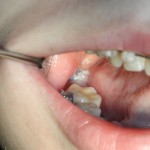

Через два дня послеоперационная рана выглядит следующим образом:

Как понимаете, пациентку ничто не беспокоит. Ну, разве, что отек немного. Он сойдет через 3-4 дня, и она спокойно продолжит работу со своим врачом-ортодонтом.

Через три месяца пациентка пришла ко мне на профилактический осмотр. Вот картинка:

Как видите, семерка делает успехи. Спасибо ортодонтам!